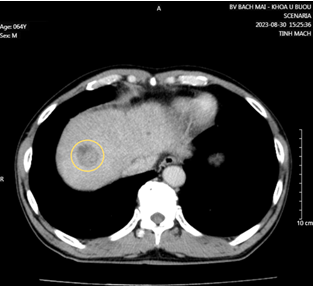

Hình 3: Nhu mô hạ phân thùy VII có vài khối, nốt kích thước lớn nhất 33x26mm giảm tỷ trọng trước tiêm, ngấm thuốc thì động mạch (vòng tròn đỏ), thải thuốc thì tĩnh mạch cửa (vòng tròn).

Cắt lớp vi tính ổ bụng có tiêm thuốc cản quang: